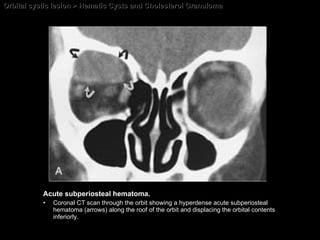

Hematic Cysts and Cholesterol Granuloma CT findings of Subperiosteal hematomas Acute hematoma  = sharply defined extraconal, homogeneous, high-density, nonenhancing mass with a  broad base abutting the bone and displacing the peripheral orbital fat .  Chronic hematoma  = sharply defined extraconal,  heterogeneous ,  relatively hypodense , nonenhancing mass.  Long-standing chronic hematic cysts  (cholesterol granulomas) = cystic lesions, associated with  compression bone atrophy  as well as expansion and erosions of adjacent bone.

Orbital cystic lesion > Hematic Cysts and Cholesterol Granuloma Acute subperiosteal hematoma. Coronal CT scan through the orbit showing a hyperdense acute subperiosteal hematoma (arrows) along the roof of the orbit and displacing the orbital contents inferiorly.